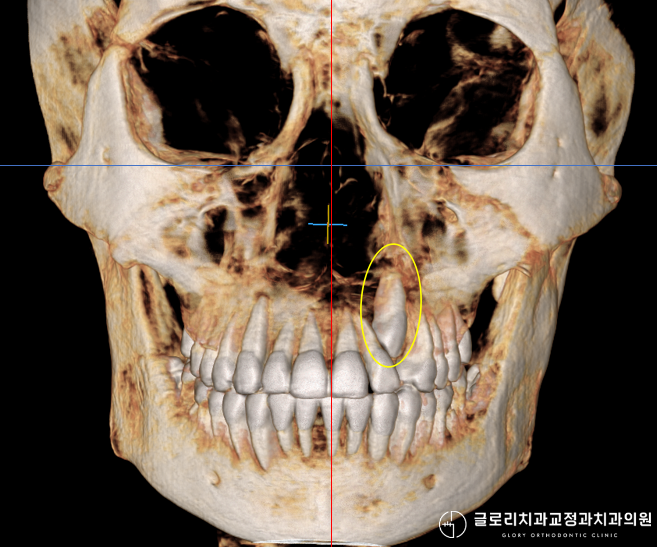

위 사진에서 확인할 수 있듯이 파노라마 엑스레이를 통해 치아 전체의 맹출 상태를 파악할 수 있습니다.

그러나 매복된 송곳니의 정확한 위치와 주변 치아 뿌리와의 관계를 확인하려면 CT 촬영이 필수적으로 병행되어야 합니다.

3차원 영상 자료를 통해 매복치가 입천장 쪽에 위치하는지 아니면 입술 쪽에 매복되어 있는지를 명확하게 구분할 수 있습니다.

이 위치에 따라 치료 방향이 달라지기 때문에 초기 진단의 정확성이 중요합니다.